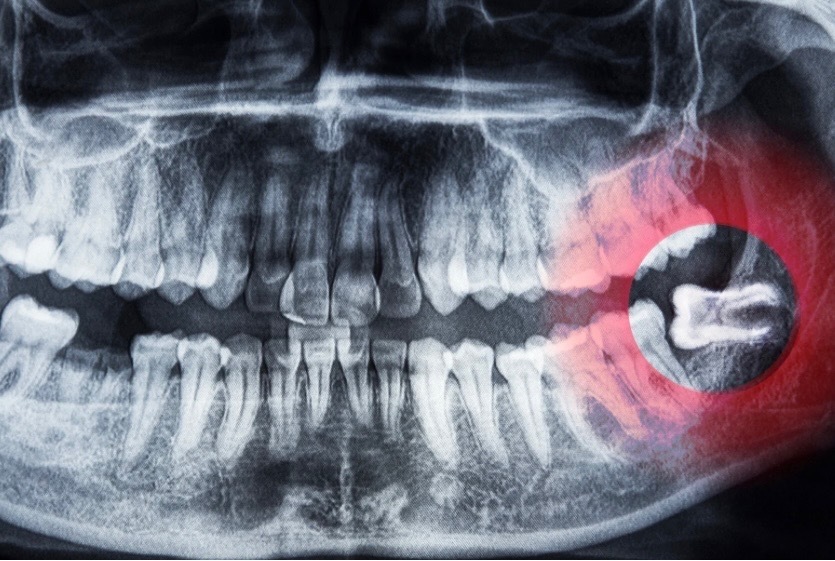

虫歯になった親知らずは抜くべき?残せる?歯科医が判断基準をわかりやすく解説

①虫歯の親知らずが抜歯される理由

親知らずが虫歯になった場合、なぜ抜歯が選ばれることが多いのでしょうか。

●きれいに生えていない

そのため、親知らずが生えるスペースが足りない場合、まっすぐに生えず、傾いていたり、歯肉に一部覆われた状態で生えてくることも珍しくありません。

このようにきれいに生えていない親知らずは、治療そのものが難しく、結果として抜歯が選択されることが多くなります。

●奇形の歯が多い

そのため歯の形が一定ではなく、とても小さな親知らずや、歯根の形が複雑な親知らずなど、いわゆる奇形の親知らずも多く見られます。

歯が小さすぎると治療ができませんし、歯根の形によっては神経の治療が困難な場合もあります。

このように、形態的な問題が多いことも、虫歯になった親知らずが抜歯されやすい理由のひとつです。